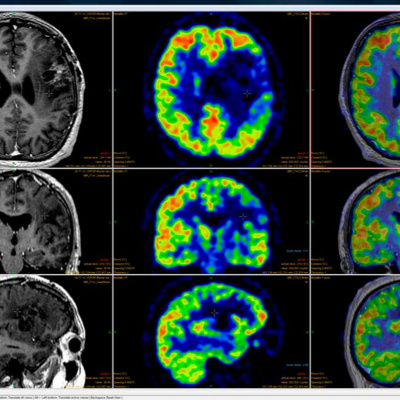

Unless you've been pretty lucky all your life, you've probably had to rely on medical imaging at some point. That could be something simple like an x-ray for a broken arm, or something more complicated like a MRI or CAT scan. Have you ever thought about how those machines work? Photons, atoms, tungsten, H2O and giant magnets for a start! Join us to find out more!